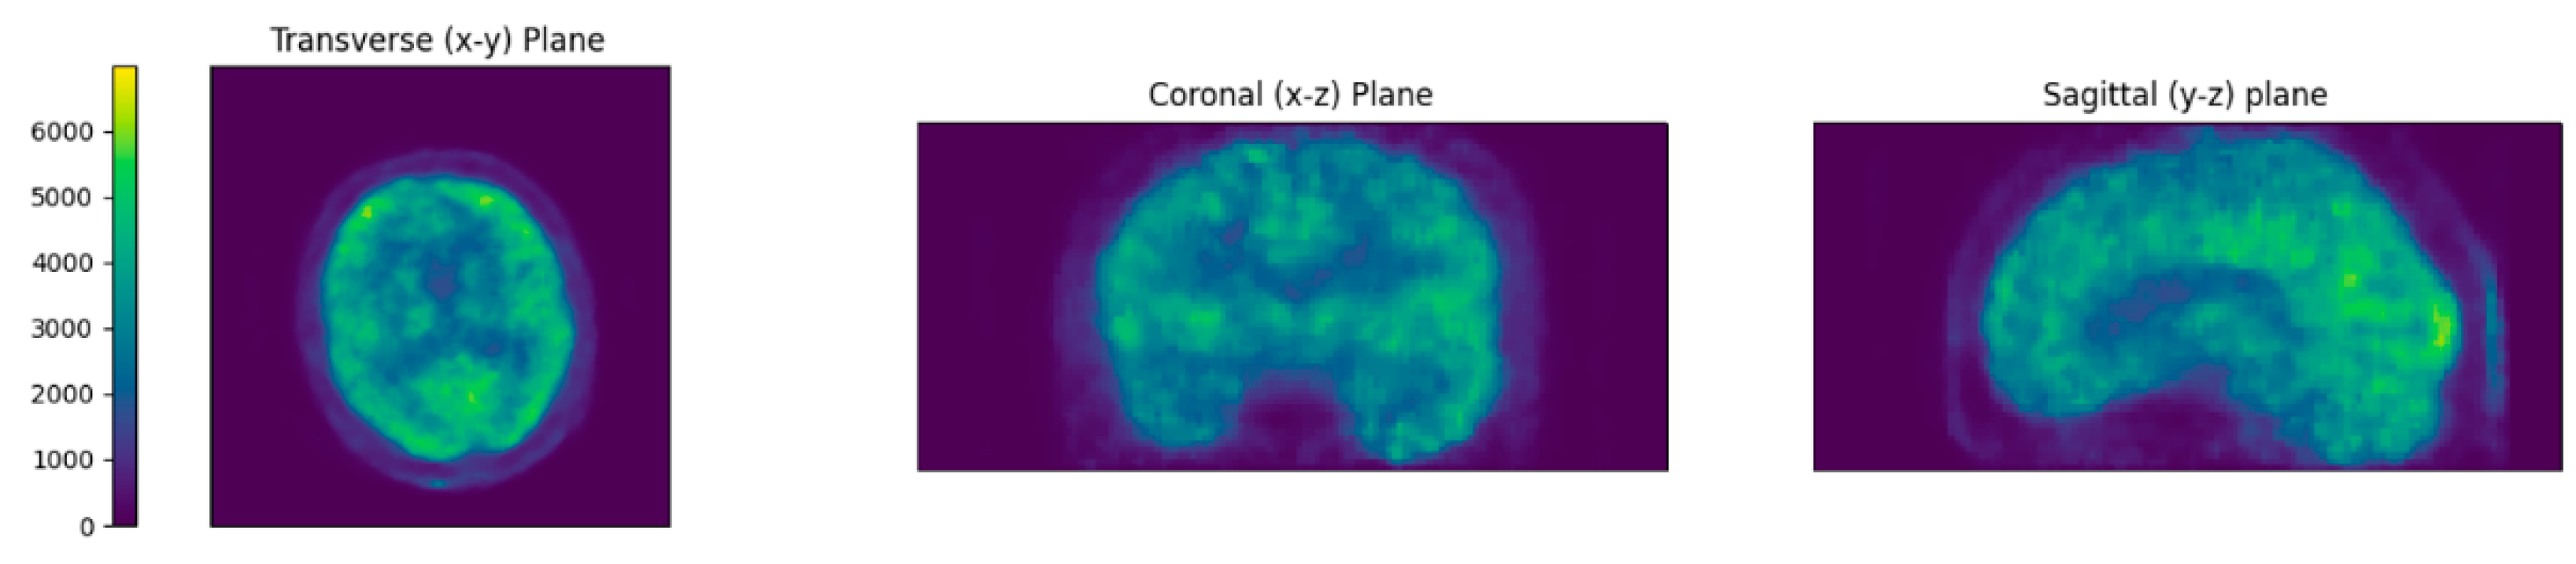

2.2.1. Image Reconstruction

3. Results

3.1. Comparison of Patient-Specific Attenuation Map vs. Generic Template Attenuation Map